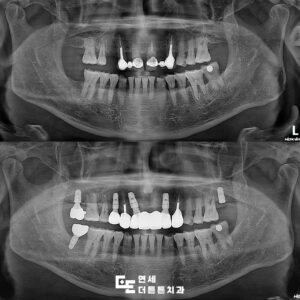

방학역치과 어금니 부위와 앞니 임플란트 수복

방학역치과 어금니 부위와 앞니 임플란트 수복 치아 상실의 위험성 치아는 평소에는 그 중요성을 크게 느끼지 못하다가도 하나씩 기능이 약해지기 시작하면 일상 속 불편함이 빠르게 커지게 됩니다. 처음에는 단단한 음식만 피하게 되는 정도로 시작되지만, 시간이 지나면 자연스럽게 씹는 힘이 약해지고 한쪽으로만 사용하는 습관이 생기기도 합니다. 특히 여러 개의 치아를 동시에 잃은 더보기…